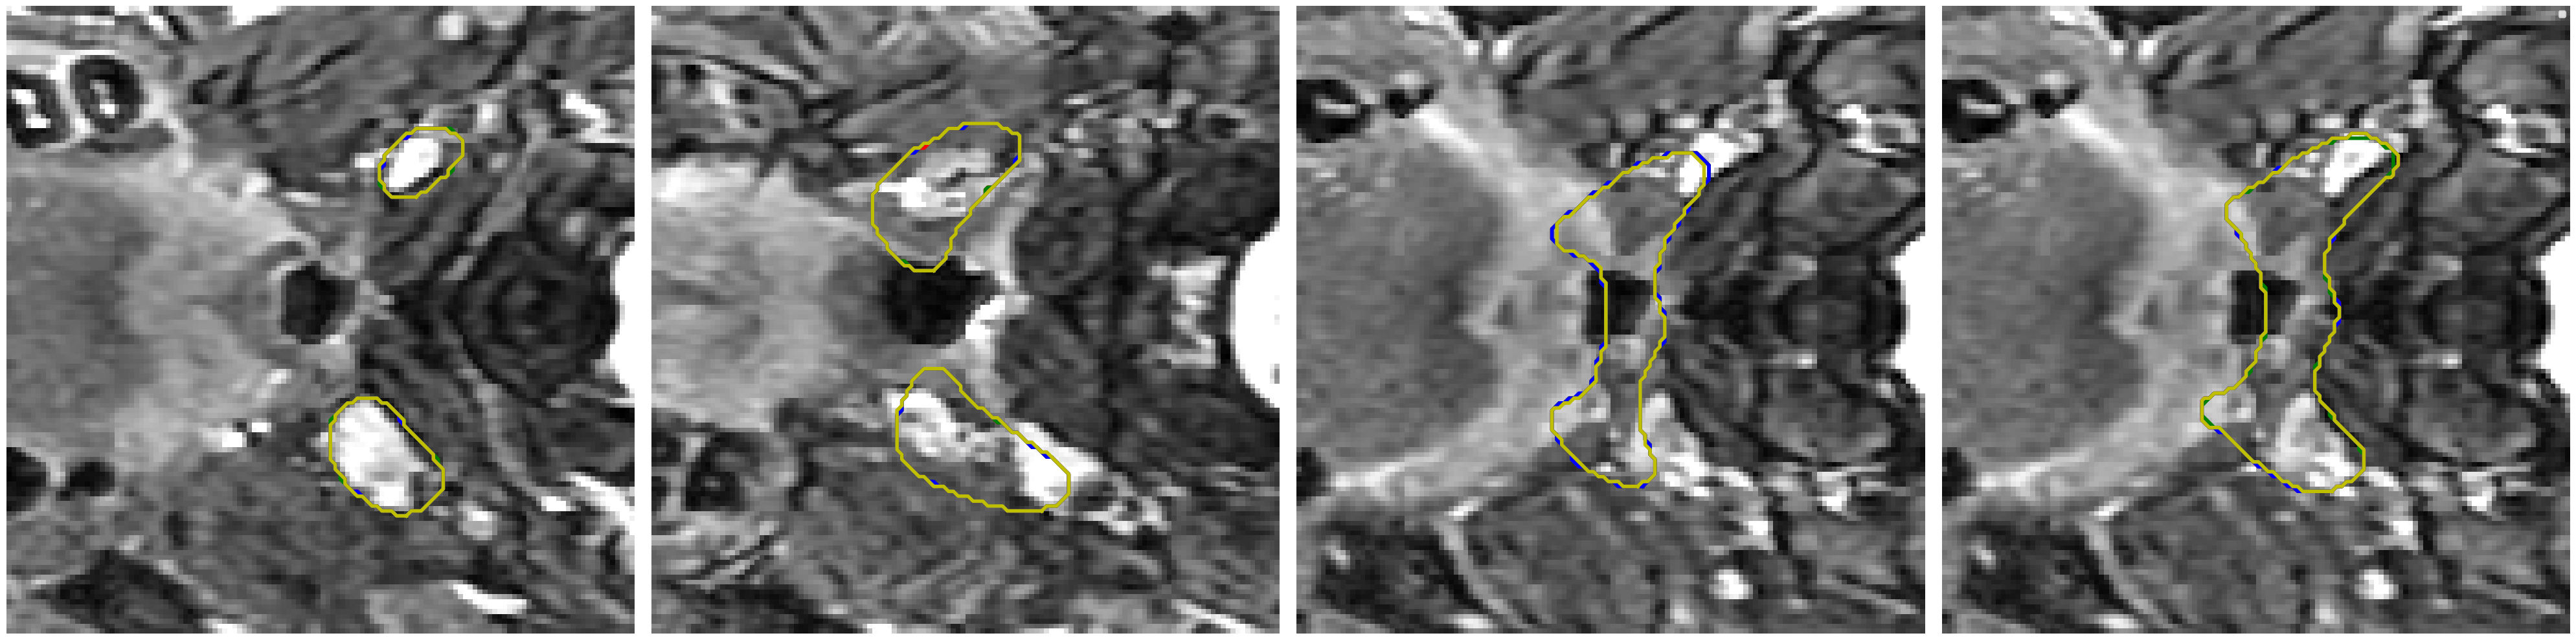

Visual comparison of segmentation results.

We provide visual comparisons of the segmentation results of all methods on the NPC dataset in Fig. 9 and Fig. 10, where different colors indicate the segmentation is obtained by different expert annotators. The segmentation results of ProSeg are more diverse and personalized than those of other methods. The segmentation results of ProSeg are more consistent with the ground truth while maintaining diversity among the generated segmentations. The results demonstrate that ProSeg effectively captures expert-specific characteristics and generates diverse segmentation results. For some methods, the segmentation from all the experts is the same, which means the diversity is poor. In Fig. 6(b), the second row shows the segmentation from our ProSeg, the third row shows the segmentation from the DPersona (stage 1) and the fourth row shows the segmentation from the DPersona (stage 2). For the second image, in the gold standard, three experts give segmentation containing two separate parts. Our ProSeg captures the character, while other models can hardly capture this difference, and generation methods can not tell which expert gives the two-part segmentation as shown in the figure that the color of the two-part segmentation is different from the Gold standard.